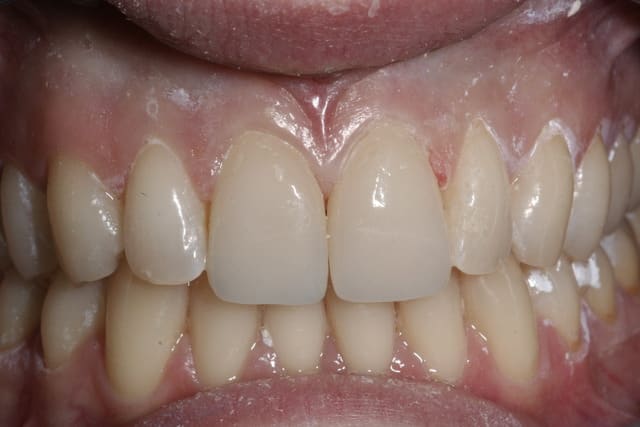

rehabilitation esthetique sur une superbe femme de 50 ans, 6 ceram sur zircone, je regrette juste de ne pas avoir fait une petite plastie gingivale sur la 11